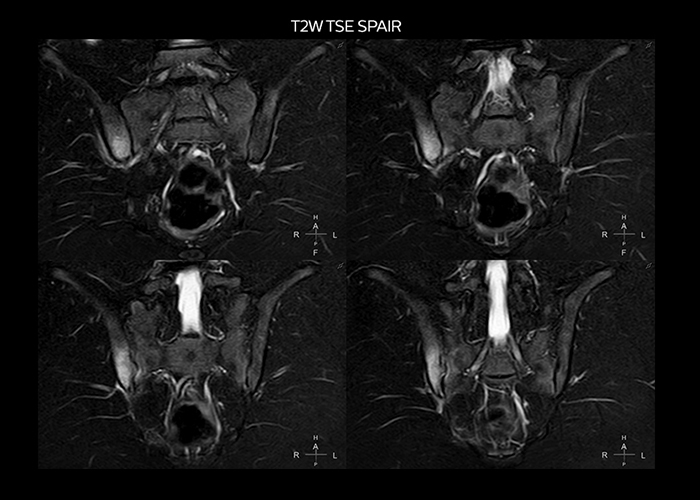

“To avoid coil changes we plan examinations of similar anatomies back to back, such as head and spine. Multiva helps us here a lot because coils don’t need to be changed frequently. Moreover, thanks to parallel imaging technology and 16-channel HeadSpineTorso and 8-channel MSK coils we are able to achieve excellent image quality. In this way Multiva helped us to increase both image quality and productivity.”

“Most important, Multiva satisfies our clinical imaging needs very well,” says Mr. Tuna. “Many features of Multiva have become similar to the Ingenia system. Even in more complex imaging such as abdominal and cardiac, the image quality and performance of Multiva is better than we expected. General surgeons and physicians from our hospital’s internal medicine department prefer to refer to us because of this.”